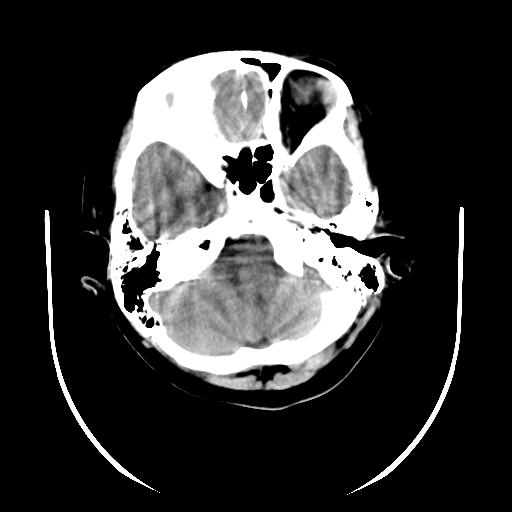

标题: PED3080:女,6岁,头痛、呕吐一天。 [打印本页]

女,6岁,头痛、呕吐一天。

颅脑ct平扫未见明显异常。

头颅ct平扫未见明确异常,随诊复查。